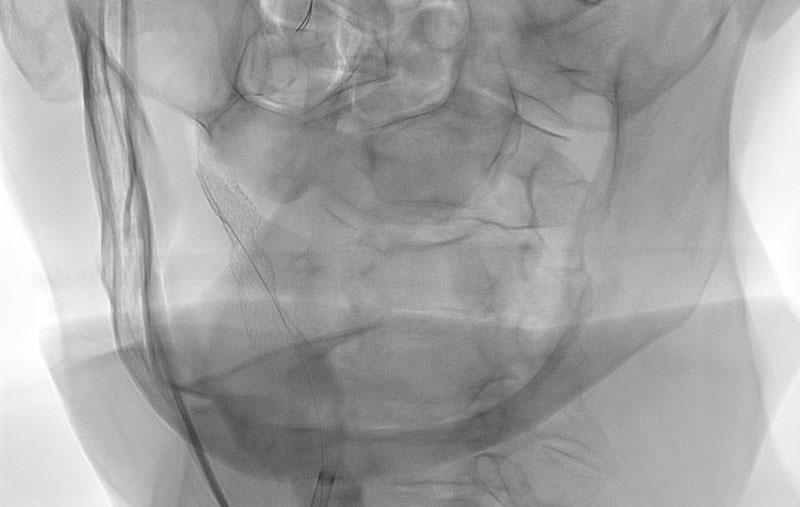

塞栓性脳梗塞

70代

救急外来

No.1469 手術前

No.1469 手術中

No.1469 手術後